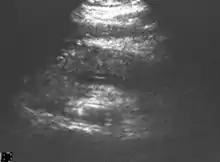

Ultrasound

On abdominal ultrasonography, the finding of a hypoechoic and bulky pancreas is regarded as diagnostic of acute pancreatitis.